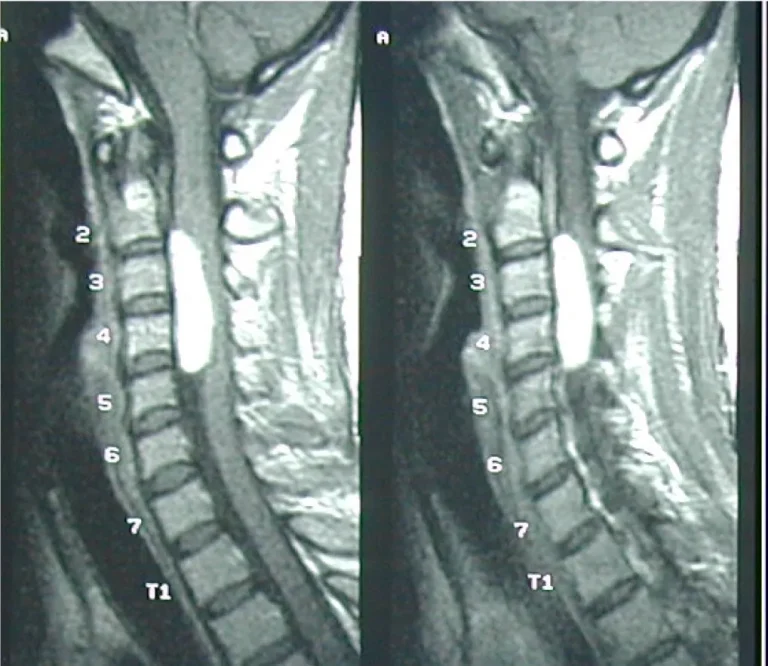

1. วินิจฉัย: ตรวจระบบประสาท + ประเมินMRI/CT : พิจารณา ตัดชิ้นเนื้อ (biopsy) หากจำเป็น

1. ส่งอาการ + ภาพ MRI/CT ผ่าน LINE OA → นัดตรวจ

ก่อนผ่า: แจ้งยาละลายลิ่มเลือด/สมุนไพร, งดน้ำอาหารตามกำหนด, นำผลMRI และ CT ล่าสุด